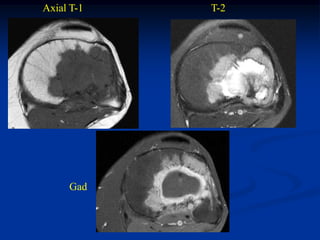

Case #218

58 year female

adamantinoma

proximal tibia

Coronal Gad

Contrast MRI

Sagittal STIR MRI

Axial T-2 MRI

Another axial T-2 MRI showing cystic fluid-fluid levels